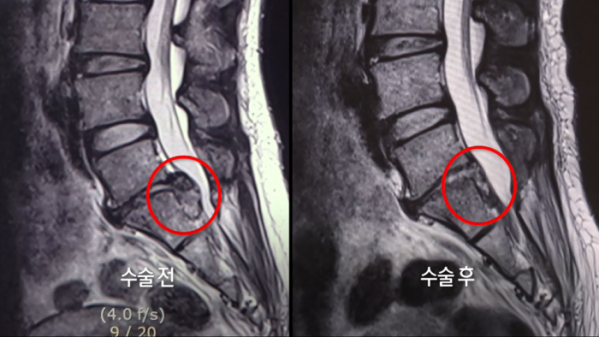

어렸을 때부터 허리가 좋지 않았다는 홍윤자 씨는 나이가 들면서 점점 허리 통증이 심해지고 병원도 다녔지만, 이제는 바닥에 앉아 있는 것조차 힘들다. 장구를 배울 때도 바닥에 앉지 못해 의자에 앉아서 쳐야 하지만, 그마저도 오래 앉아 있지 못한다. 사무직으로 일을 하는 강지현 씨 또한 평소 일하는 자세가 바르지 않았고, 좋지 않은 자세로 장시간 일하다 보니 허리에 무리가 왔고 결국 추간판 탈출증 수술까지 하게 되었다.